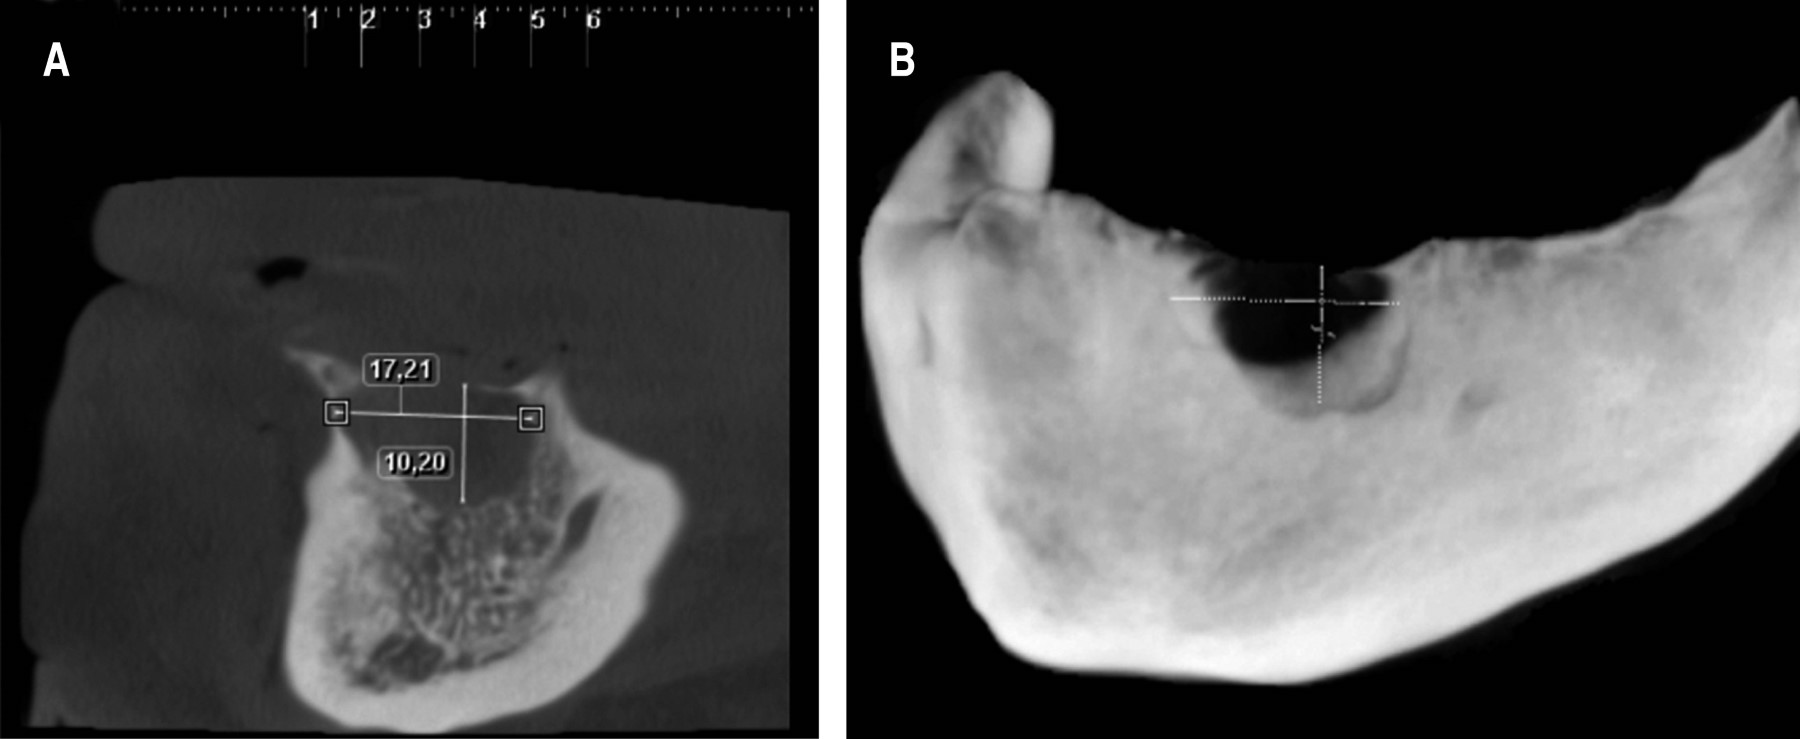

Al examen físico se observa un tumor de 25 mm de diámetro mayor en el reborde edéntulo mandibular anterior, de consistencia firme, indoloro, con abombamiento de tablas óseas y color rojo-violáceo (Figura 1). Se solicita una tomografía computarizada Cone Beam, en la cual se observa una lesión osteolítica inmediatamente a la izquierda de la línea media mandibular de 17.2 × 10.2 mm y que perfora la tabla ósea vestibular y lingual (Figura 2). El paciente había consultado un año antes por esta misma lesión, sin embargo, no acude a los controles para completar el estudio y planificar su tratamiento.

Figura 2